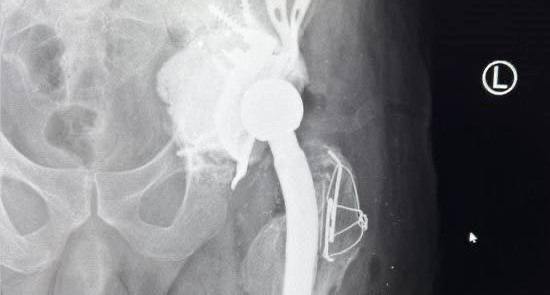

Обследование выявило сложный перелом со смещением, сильную кровопотерю и болевой синдром. Ситуацию осложнило повреждение ранее установленного тазобедренного протеза: его элементы пробили тазовое дно, а металлические фрагменты оказались опасно близко к органам малого таза.

«Операция длилась долгих 8 часов и потребовала особой осторожности и точности. При данном виде травмы из-за сильного кровотечения пациенту дважды переливалась кровь — перед началом хирургического вмешательства и во время операции. Сначала мы извлекли компоненты старого протеза, после чего в тазовую кость установили специальную конструкцию в виде каркаса, что позволило создать точку опоры для крепления нового сустава. Собрали перелом бедренной кости, установив новый тазобедренный сустав», — рассказал врач-травматолог Дубненской больницы Максим Калинкин.